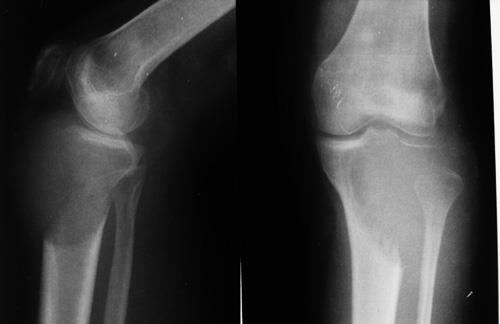

4)骨巨细胞瘤

①20-40岁成人(3/4),10岁以下儿童罕见

②股骨下端最多见,其次为胫骨上端及桡骨下端,三处占全部骨巨细胞瘤的60-70%

③病灶位于骨端,邻关节面(不累及骼后的骨细胞瘤诊断基本不成立)

④病灶延伸至骨突内

⑤手术治疗

slide0068_image064